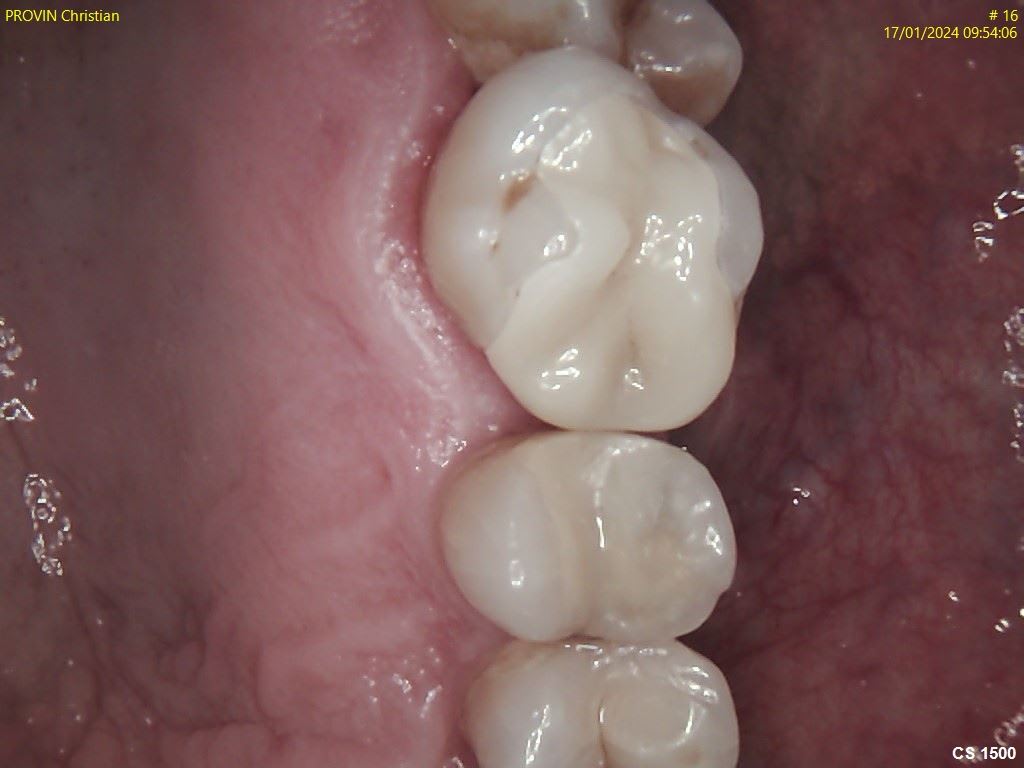

je teste en zircone avec la panavia cement universal. Images avant et après collage